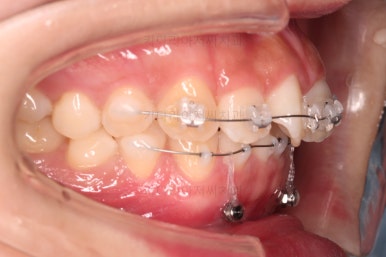

아래 앞니는 브라켓보다는 훨씬 작은 미니튜브 장치를 사용했습니다.

과개교합의 경우 브라켓을 부착하게 되면 씹히게 되어 치료과정이 수월하지 못하기 때문이죠.

디테일을 위해서 윗니는 어금니에도 하나씩 장치를 더 부착했고, 아랫니는 바로 뒷 치아에도 장치를 부착했습니다.

기왕(부분교정임을 감안했을 때) 오래 걸린거 좀 더 완성도를 높이고자 아래 앞니는 설측교정까지 부착했습니다.

역시 미니튜브 장치를 이용했고, 아래 앞니 안쪽에다가 장치를 부착해서 아주 미세한 배열을 맞춰드렸습니다.

다시 틀어지지 말라고, 철사형 유지장치를 부착했고요.

과개교합이 재발되지 말라고 특수한 형태의 유지장치를 추가로 만들어드렸습니다.